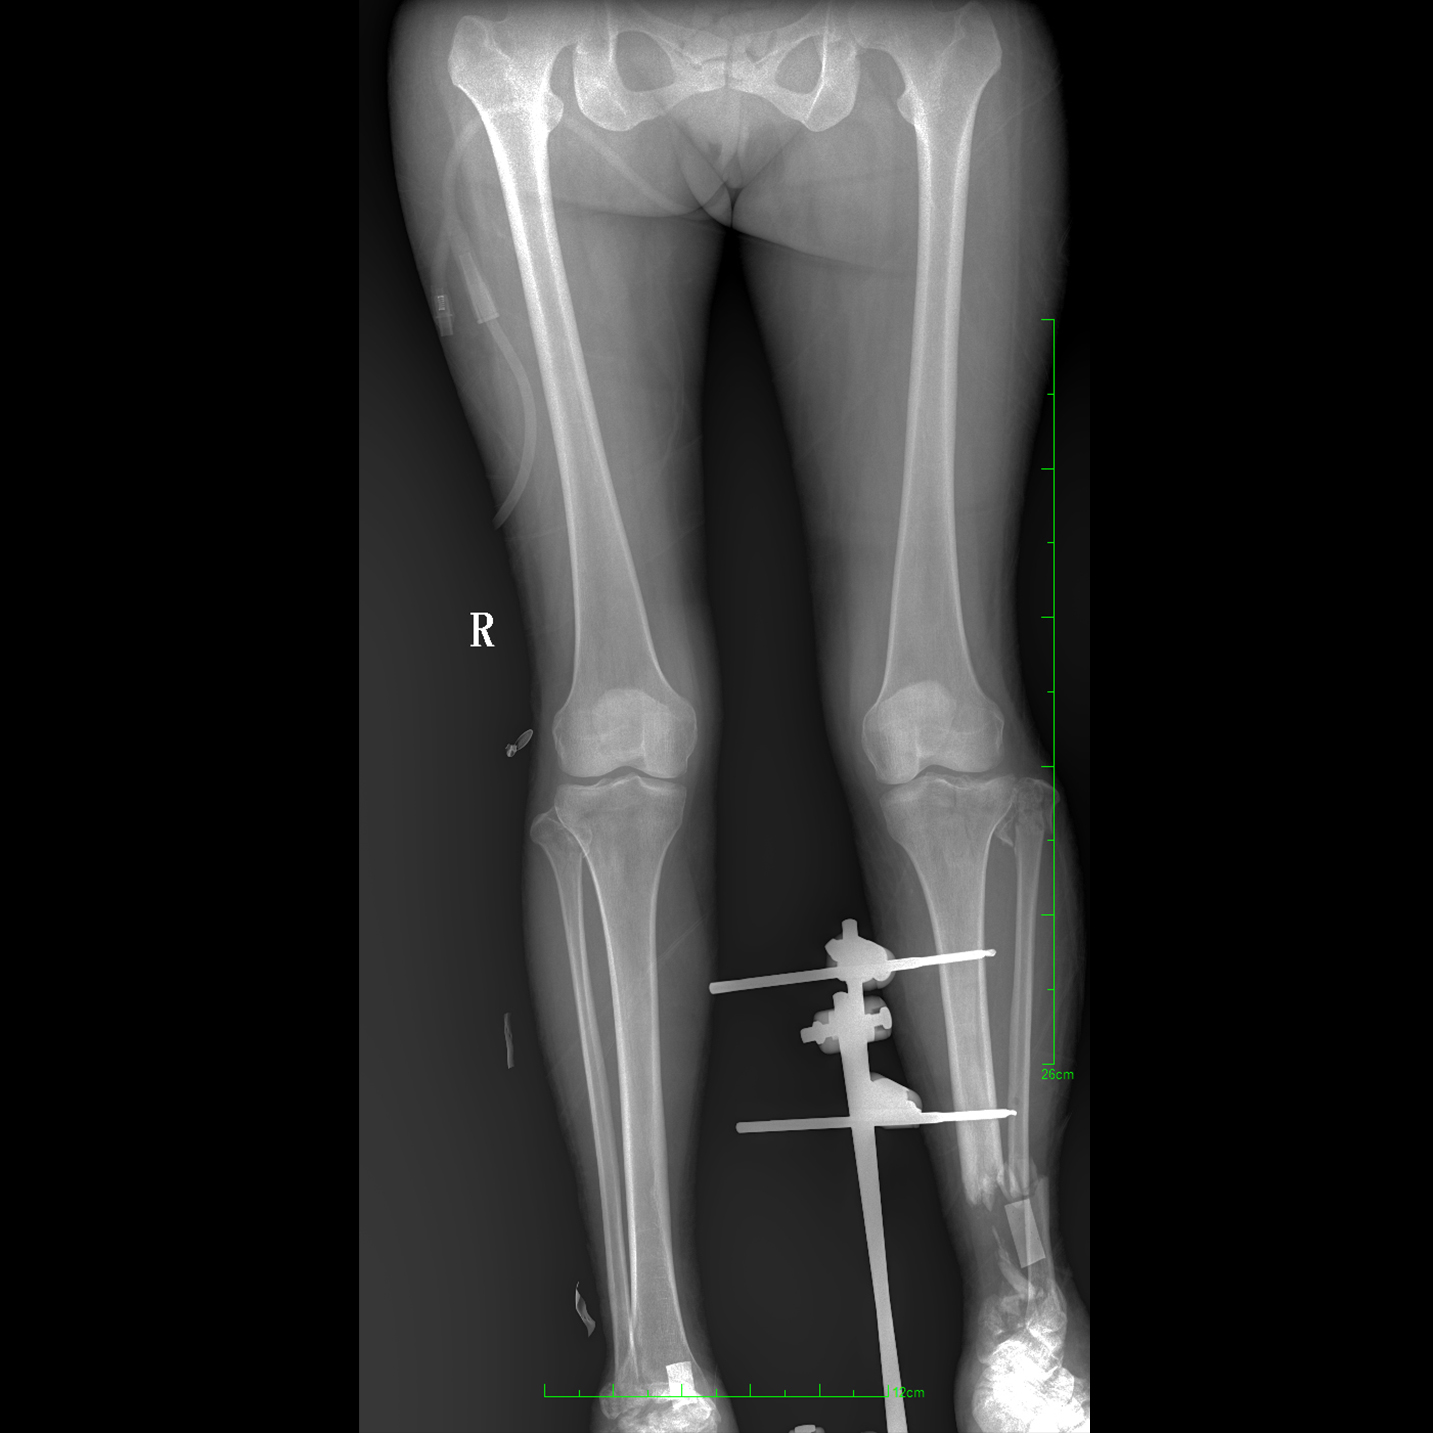

支持全脊柱攝影、雙下肢攝影、脊髓造影、復(fù)雜創(chuàng)傷、人工關(guān)節(jié)置換、關(guān)節(jié)損傷的修復(fù)重建等大視野臨床應(yīng)用

全脊柱一次成像 不拼接

17"*34"有效視野,一次成像不拼接。相較于多張攝影再軟件拼接的DR設(shè)備,PLX8600解決了拼接圖像存在密度不均勻,拼接處圖像配準(zhǔn)和放大效應(yīng)等問題,給臨床帶來了大視野影像解決方案,可一次性覆蓋全脊柱或雙下肢影像。

Clinical picture

臨床圖片